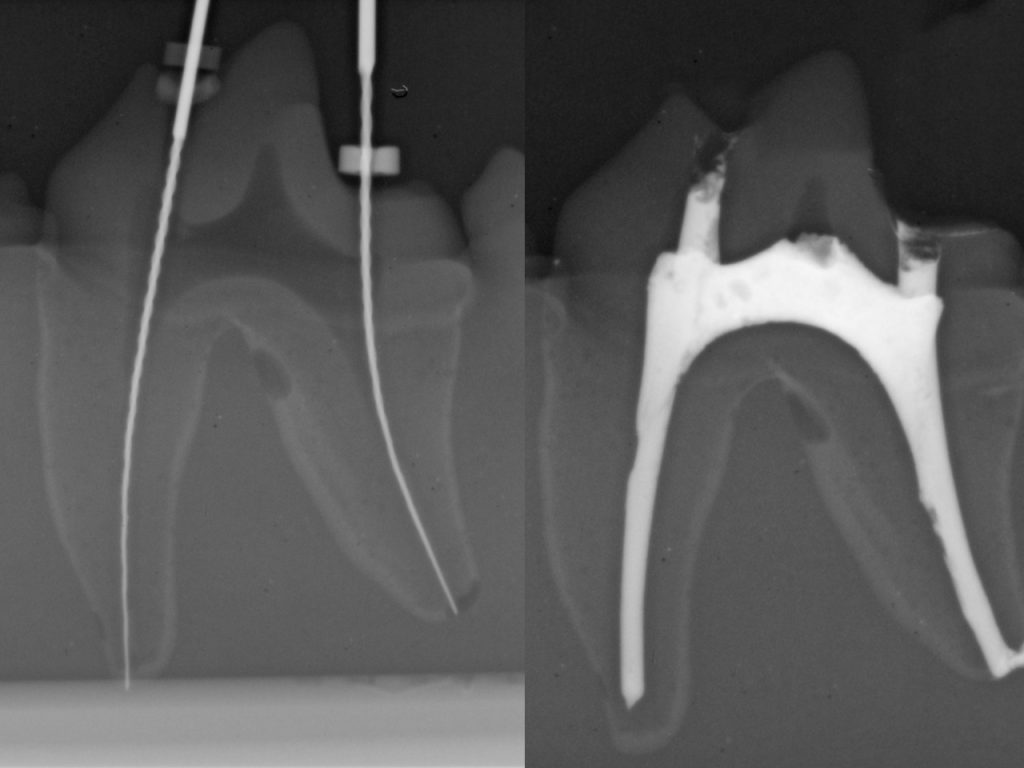

Slow dental X-rays? Perform full-mouth exams in minutes

Still struggling with dental X-rays? Fix it today